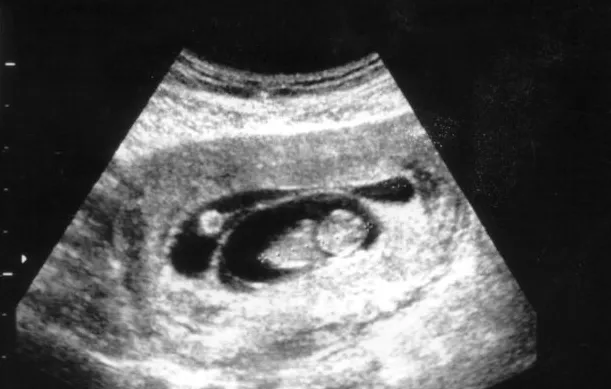

Vanaf vandaag mogen partners dus nog steeds maar beperkt mee als er bijvoorbeeld een echo wordt gemaakt. 'In het ziekenhuis blijft voorlopig de regel: kom alléén naar uw afspraak , ' aldus het ZMC. Het algemene beleid is daar dat alle pariënten in hun eentje komen, met uitzondering van kinderen, kwetsbare mensen en mensen die een tolk nodig hebben. Die mogen zich door één persoon laten begeleiden. Alle patiënten die het ziekenhuis bezoeken wordt gevraagd de duur van hun verblijf zoveel mogelijk te beperken. Dus niet te vroeg komen en na het consult meteen weer vertrekken.